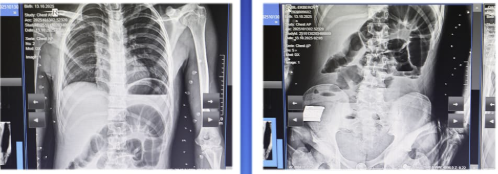

Bakıda 17 yaşlı yeniyetmə taxta udaraq qarın nahiyəsində kəskin ağrı, ürəkbulanma, təkrarlanan qusma və hipertermiya şikayətləri ilə Kliniki Tibbi Mərkəzin (KTM) Təcili və Təxirəsalınmaz Tibbi Yardım şöbəsinə gətirilib.

Bildirilib ki, müayinələr nəticəsində xəstəyə peritonit diaqnozu qoyulub və əməliyyatönü hazırlıqdan sonra təxirəsalınmaz cərrahi müdaxilə aparılıb. Nazik bağırsaq seqmentinin rezeksiyası, yoğun bağırsağın defektinin tikilməsi əməliyyatı icra olunub.

Əməliyyat zamanı nazik bağırsaqda, iliosekal küncdən 70–80 sm məsafədə, iki yerdə deşici (perforativ) zədələnmə müəyyən olunub. Bu perforasiyalara səbəb bağırsaq mənfəzində yerləşən iti və sərt yad cisim taxta parçası olub. Bundan əlavə, yoğun bağırsaqda da perforativ dəlik və bütün nazik bağırsaq boyunca mənfəz daxilində müxtəlif ölçülü, iti uclu, sərt yad cisimlər aşkarlanıb.

Uğurlu cərrahi müdaxilə və 8 günlük stasionar müalicə nəticəsində xəstənin vəziyyəti kafi qiymətləndirilib və o, ambulator müalicə üçün evə buraxılıb.